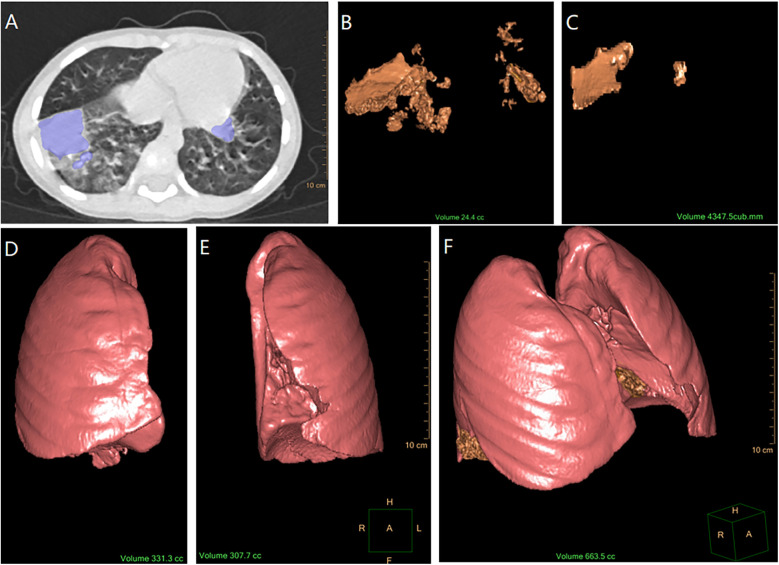

Results: Among 238 children with MPP and lung consolidation, females slightly outnumbered males (129 vs. 109), with a mean age of approximately 5 years. Most children received azithromycin as the first-line treatment. Lung consolidation accounted for 4.48% (IQR: 2.61%-7.35%) of the total lung volume pre-treatment, with an absorption rate of 96.08% (IQR: 88.02%-98.95%) observed during follow-up at a median interval of 17 days (IQR: 15-21 days). The median absorption speed was 2.15 cc/day (IQR: 1.23-4.01 cc/day), with complete absorption occurring within 18.96 days (IQR: 16.14-23.33 days). Comparative analysis of the BAL and non-BAL groups revealed significant differences in fever duration, hs-CRP levels, consolidation-to-total lung volume ratio at admission, follow-up intervals, and consolidation absorption speed. Following 1:1 propensity score matching (PSM) to control for confounding factors, a statistically significant but small-to-medium effect persisted, with the median absorption rate remaining higher in the BAL group (2.13 cc/day) compared to the non-BAL group (1.60 cc/day).

Conclusions: Using CT scan to evaluate consolidation changes in children with Mycoplasma pneumonia, most children have 96% resolution within 2-3 weeks timeframe. Those who had a bronchoscopy may have a faster resolution rate but undertaking a flexible bronchoscopy under these circumstances is not a standard procedure in most settings.